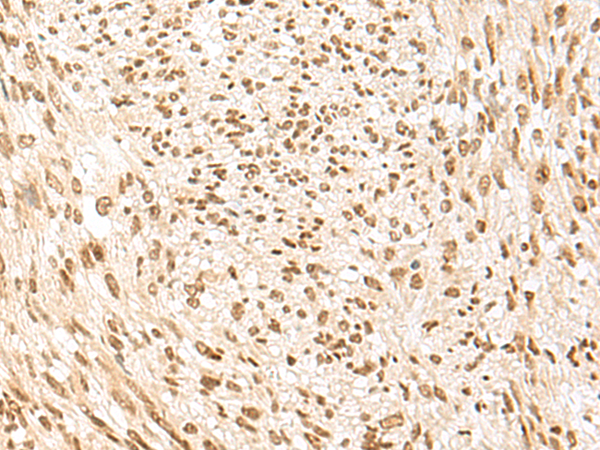

分类: 科研抗体货号: P09960别名: PC5; PC6; PC6A; SPC6应用: IHC反应种属: Human, Mouse, Rat